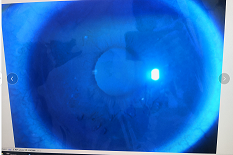

圓錐角膜要做那種治療比較好

【文章導(dǎo)讀】圓錐角膜的治療應(yīng)該依據(jù)角膜發(fā)展的時(shí)期選擇。目前圓錐角膜按照臨床癥狀大致可以分為四個(gè)時(shí)期,分別為潛伏期、初發(fā)期、完成期和瘢痕期,各個(gè)時(shí)期的主要癥狀表現(xiàn)如下: 潛伏期:

圓錐角膜的治療應(yīng)該依據(jù)角膜發(fā)展的時(shí)期選擇。目前圓錐角膜按照臨床癥狀大致可以分為四個(gè)時(shí)期,分別為潛伏期、初發(fā)期、完成期和瘢痕期,各個(gè)時(shí)期的主要癥狀表現(xiàn)如下:

潛伏期:癥狀不明顯。

初發(fā)期:開始近視,同時(shí)散光和不規(guī)則散光度數(shù)也會(huì)逐漸增加。

完成期:發(fā)展迅速,角膜明顯前突,視力銳減。

瘢痕期:角膜急性角膜水腫、混濁,消退后基質(zhì)層殘留瘢痕。

對于對于進(jìn)展非常慢,可能幾年曲率都不變化的圓錐角膜,可以觀察隨診,或者佩戴RGP矯正。如果角膜發(fā)展較快,近視散光度數(shù)增加較快,則需要通過角膜交聯(lián)來治療。

圓錐角膜的形成機(jī)制就是膠原變薄,變?nèi)?。圓錐角膜患者的角膜膠原變薄了以后,彈性增加,正常的眼壓會(huì)使角膜向前膨隆。

角膜膠原交聯(lián)手術(shù)可以通過藥物,維生素B2和紫外線交聯(lián),使角膜里面的膠原纖維的硬度增加,在對抗正常眼壓情況下,對抗力增加。交聯(lián)后角膜的韌度增加,就不容易再往前繼續(xù)發(fā)展。

但如果已經(jīng)發(fā)展到圓錐后期,再去交聯(lián)就沒有意義,就只能通過角膜移植手術(shù)治療,把向前凸起的角膜給切掉,換成新的角膜。

目前圓錐角膜的治療方式主要就是配鏡矯正、角膜膠原交聯(lián)手術(shù)以及角膜移植手術(shù)這幾種。